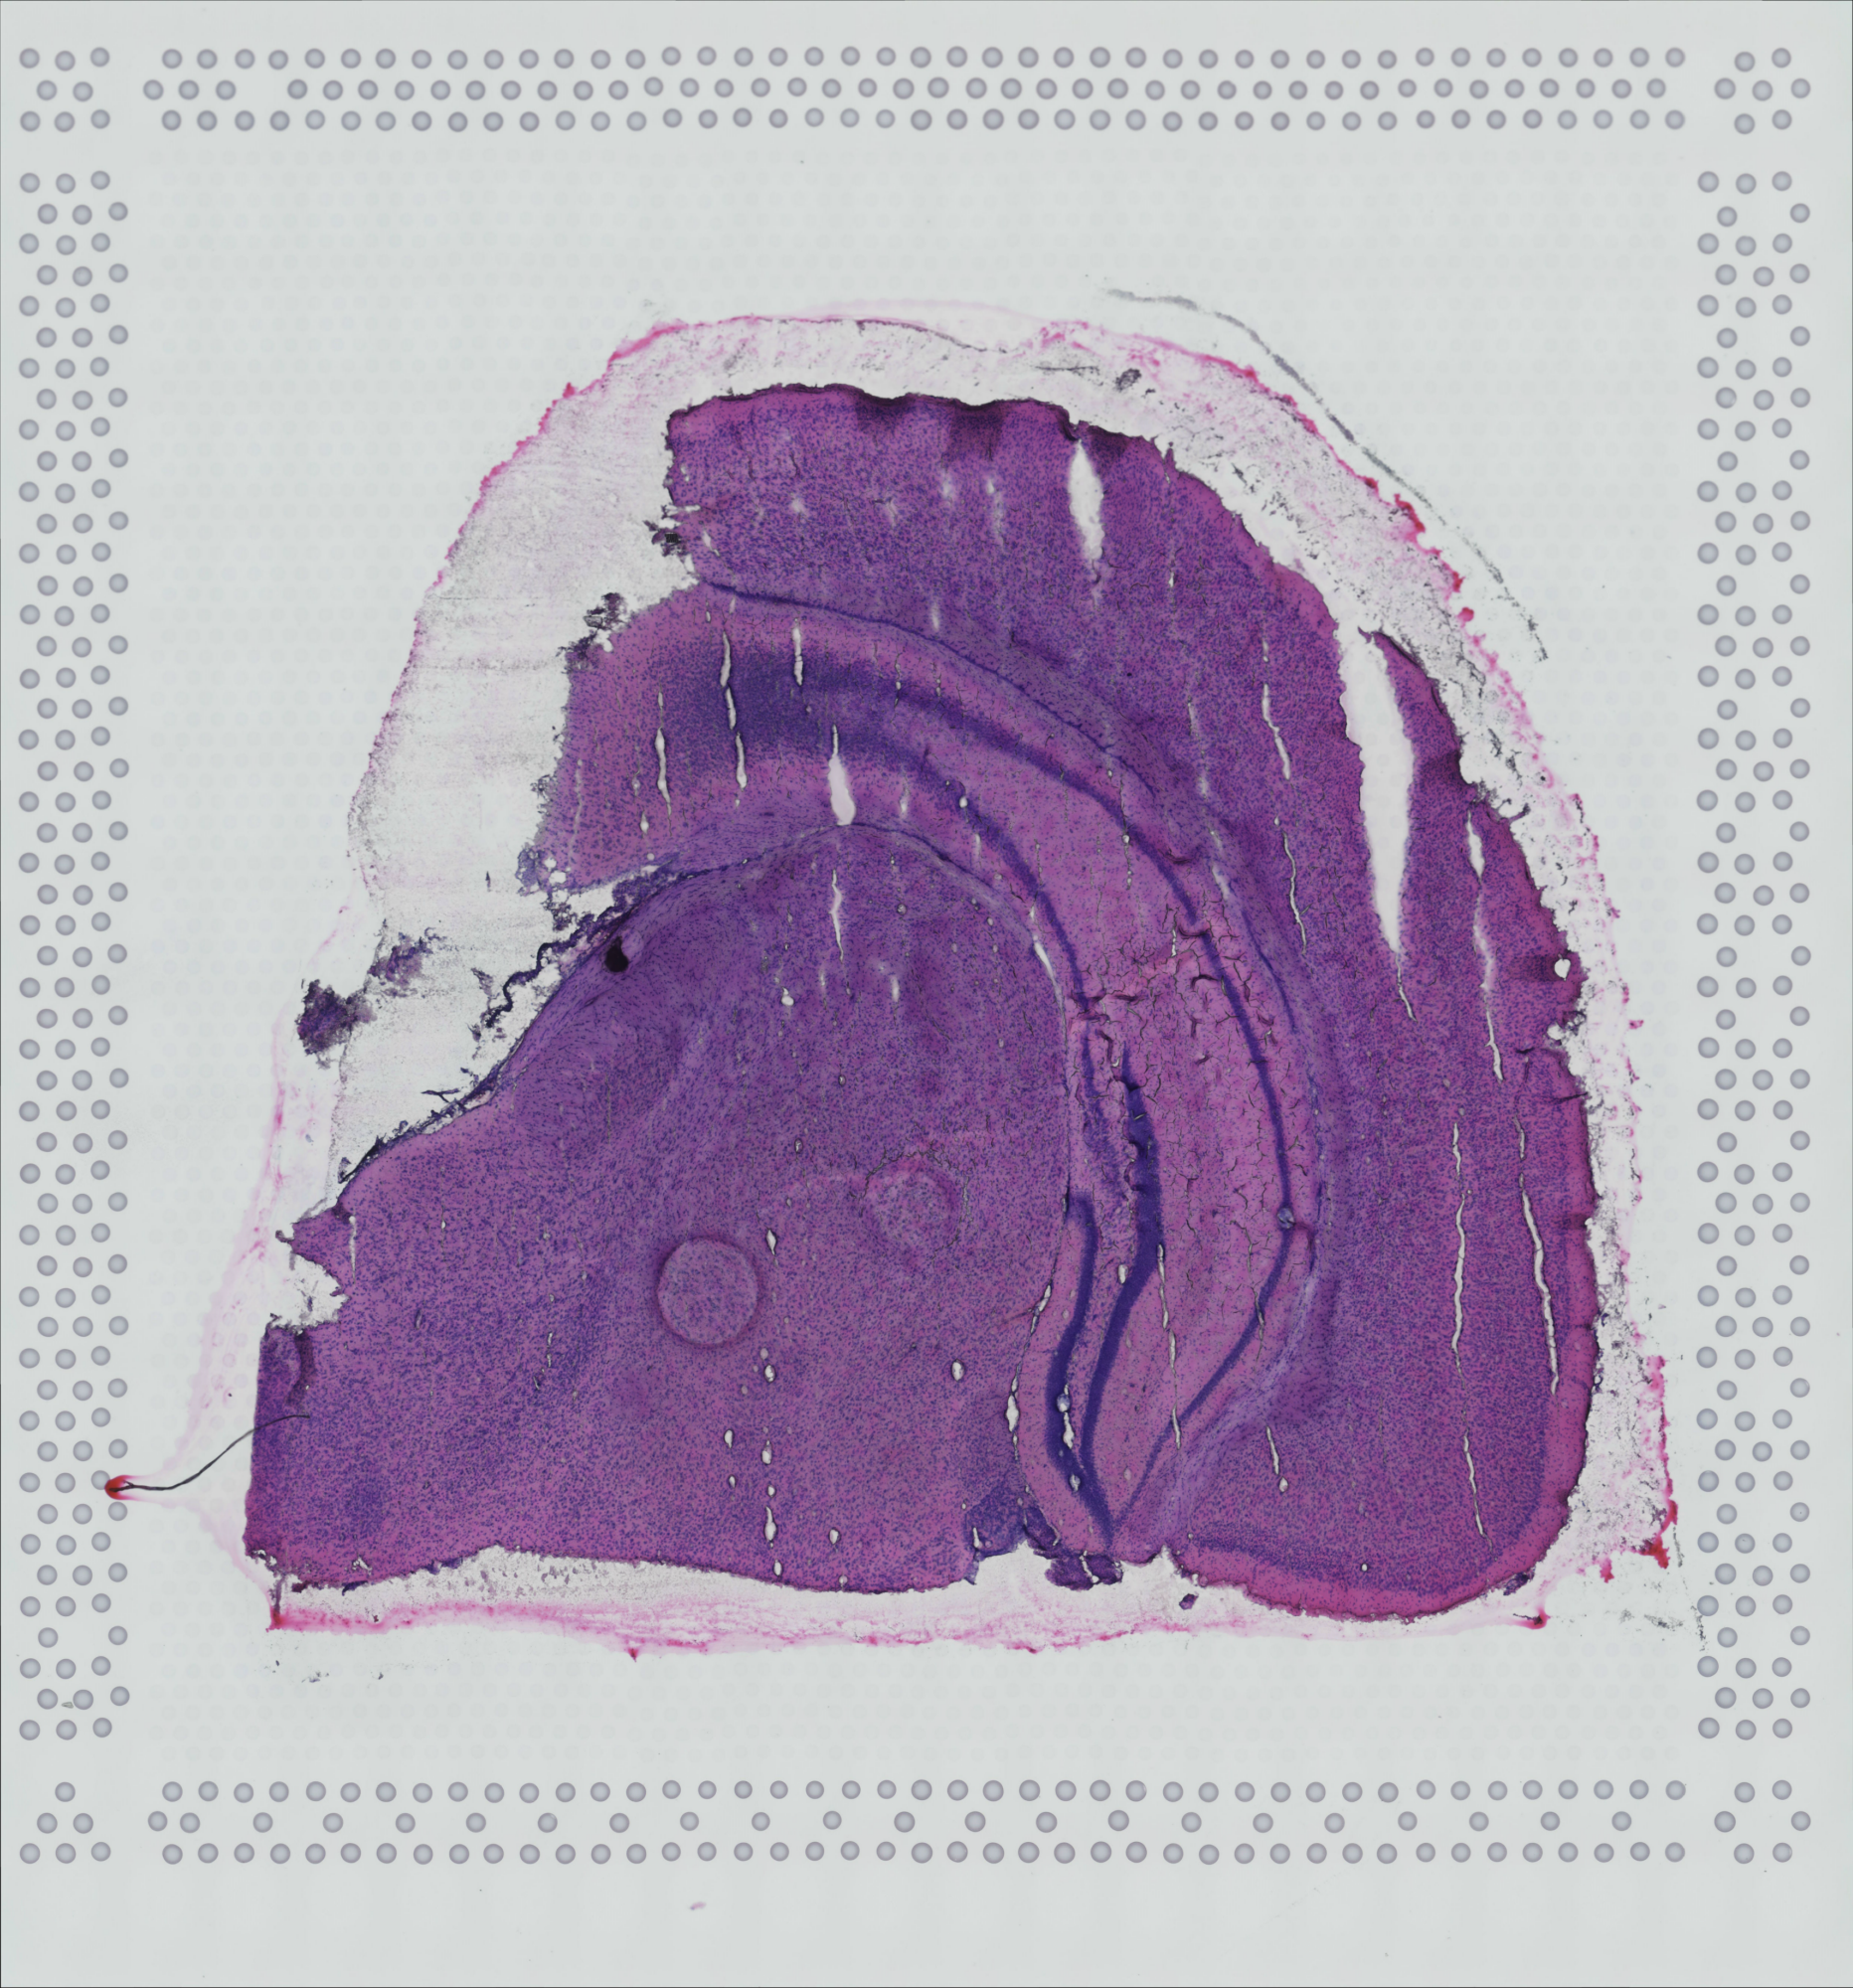

tissue_hires_image.png